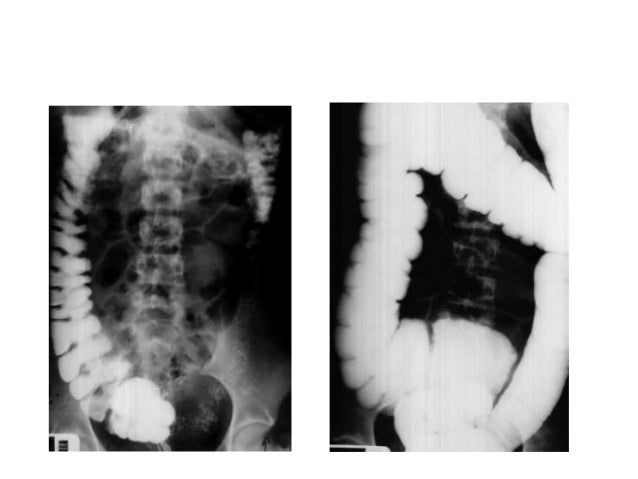

However stenosis with concentricity of the fold was observed in the cecum which was shifted upward and to the left. The patients symptoms resolved quickly after colonoscopic reduction and elective laparoscopic surgery was performed 18 days after admission. This report details the case of a patient with a mobile cecum associated with hEDS.

The patients symptoms resolved quickly after colonoscopic reduction and elective laparoscopic surgery was performed 18 days after admission. A planned surgery is not fun but an emergency surgery for a twisted colon would be even worse. Based on these findings we diagnosed cecal volvulus caused by mobile cecum syndrome. On the other hand a chronic form of mobile cecum syndrome which is the most common form reported a history of intermittent crampy abdominal pain distension and constipation. However it may be present as a precursor of frank cecal volvulus in approximately 50 per cent of the cases. 102 patients were followed up to 15 years after the operation. Abstract Five cases of mobile cecum syndrome are presented. Ehlers-Danlos syndrome hypermobility type EDS-HT mobile cecum ptosis laparoscopic. The following symptoms may be experienced with cecal volvulus.

On the other hand a chronic form of mobile cecum syndrome which is the most common form reported a history of intermittent crampy abdominal pain distension and constipation. It lies at the junction of the small and the large intestines and is the origin of the appendix. Ballooning abdomen abdominal distension. Thats about as mobile as you can get. The following symptoms may be experienced with cecal volvulus. A mobile caecum and ascending colon is a rare congenital abnormality. The cecal volvulus represents the acute form with typical feature of a bowel obstruction that needs immediate operative treatment.